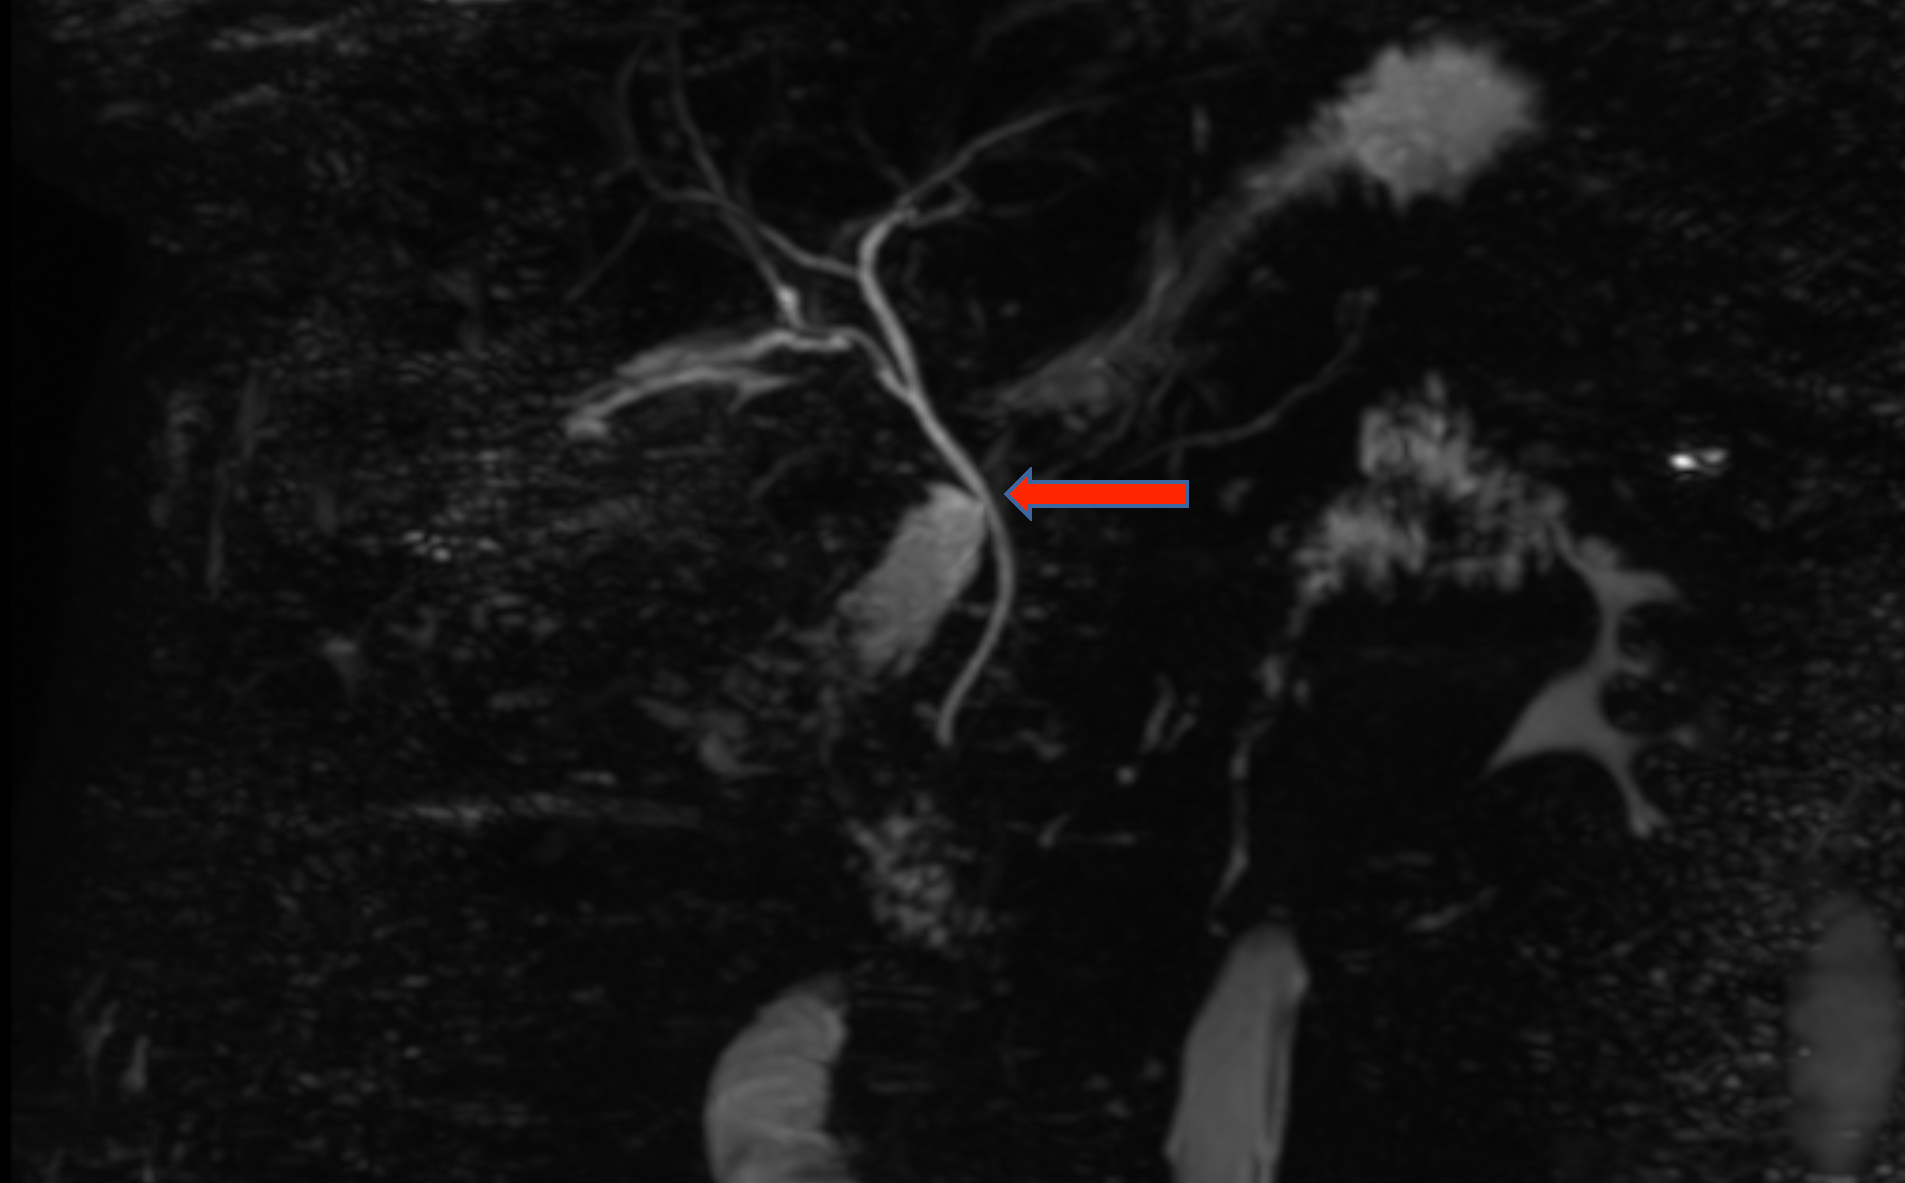

Magnetic Resonance Cholangiopancreatography (MRCP) was done, which showed leakage of bile from the common bile duct (CBD) (Figure 1). There was no bile leak from any other site. A plan for Endoscopic Retrograde Cholangiopancreatography (ERCP) was made, which also showed a side rent in the CBD, and biliary stenting was done. On the second day after ERCP, bile discharge occurred again from the wound. Repeat MRCP showed leakage of bile from a bile duct, which was running in the gallbladder fossa, draining into the common hepatic duct (Figure 2). After describing the situation to the patient and taking informed and written consent, a plan of exploration was made. On re-exploration through the Kocher’s right subcostal incision, three clips were found in the gallbladder fossa with a small collection. There was a leakage of bile from a minor opening in the bile duct running through the liver bed in the gallbladder fossa. This rent was closed with Polydioxanone 5/0 suture. Subhepatic drain was placed, and the abdomen was closed. The postoperative course of the patient remained uneventful with no biliary discharge in the drain, which was removed on the 4th postoperative day, and the patient was discharged in a haemodynamically stable condition.

Figure 2: MRCP showing bile leak from the duct of Luschka draining into the common bile duct (red arrow).